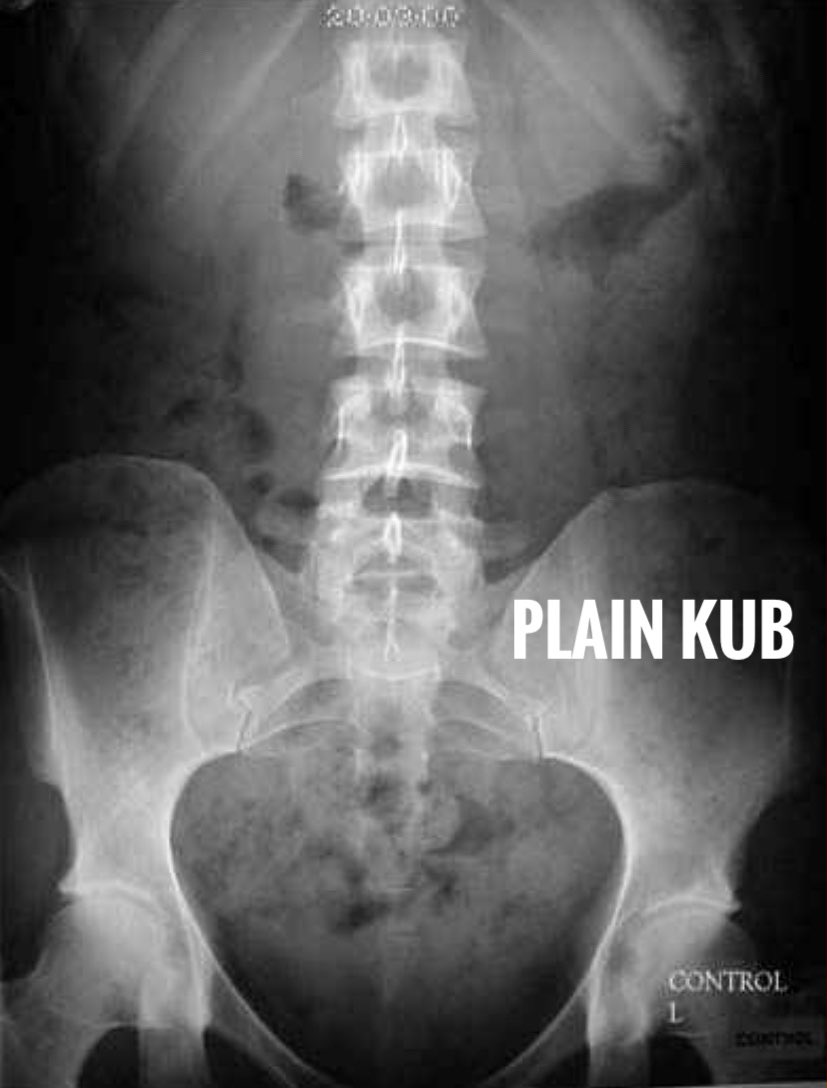

Definition : its a radiographic examination by contrast media to image the kidney - ureter - urinary bladder.

I.V.U = intravenous urography

I.V.P = Intravenous pyelography

منتقل الان لفحص الكلى : الفحص يكون على مراحل ولكل مرحله وقت معين وتقسيمها كالاتي :

- nephtogram phase ( 5min )

- compression bad phase ( 10 to 15 min )

-release phase ( 25 min )

- post micturition